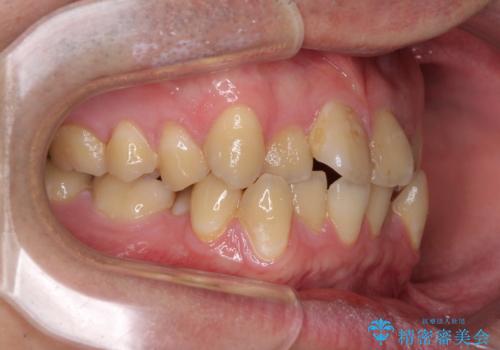

- 上下のデコボコと前歯のクロスバイトを改善したいとのことで来院された患者様です。

マウスピース矯正での自己管理には自信がないとのことで、ワイヤー装置による矯正治療を行うこととしました。

デコボコの程度は強かったのですが、口元の突出感はなかったため、非抜歯矯正としました。

クロスバイトは、治療の過程で咬み合わせが大きく変化する期間があり、食事が取りにくくなってしまいます。

また、装置が対合歯と咬み合ってしまい、頻繁に脱落するなど、色々と面倒なことがあり、治療がスムーズに進まないことがあります。